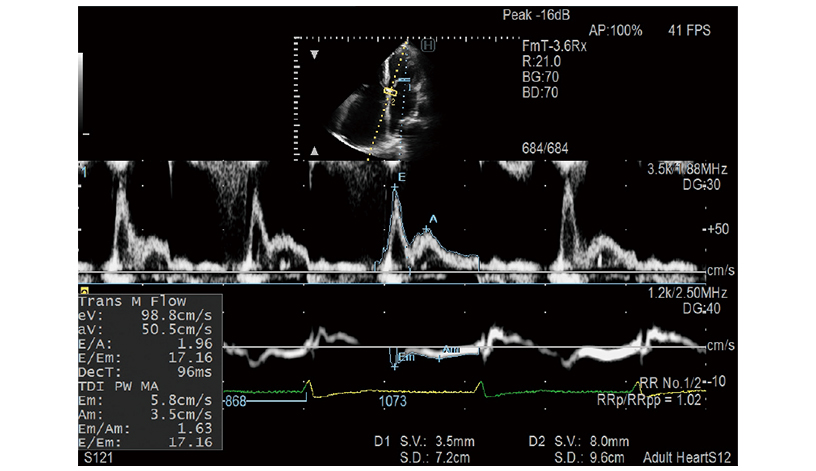

- Doppler Cursor Assist: Auto setting of sample gate position

E/e', one of the key LV diastolic performance indices, is measured automatically in Dual Gate Doppler. By using this in combination with R-R Navigation, Using this feature in combination with R-R Navigation, iDGD detects an appropriate heartbeat for measurement automatically.